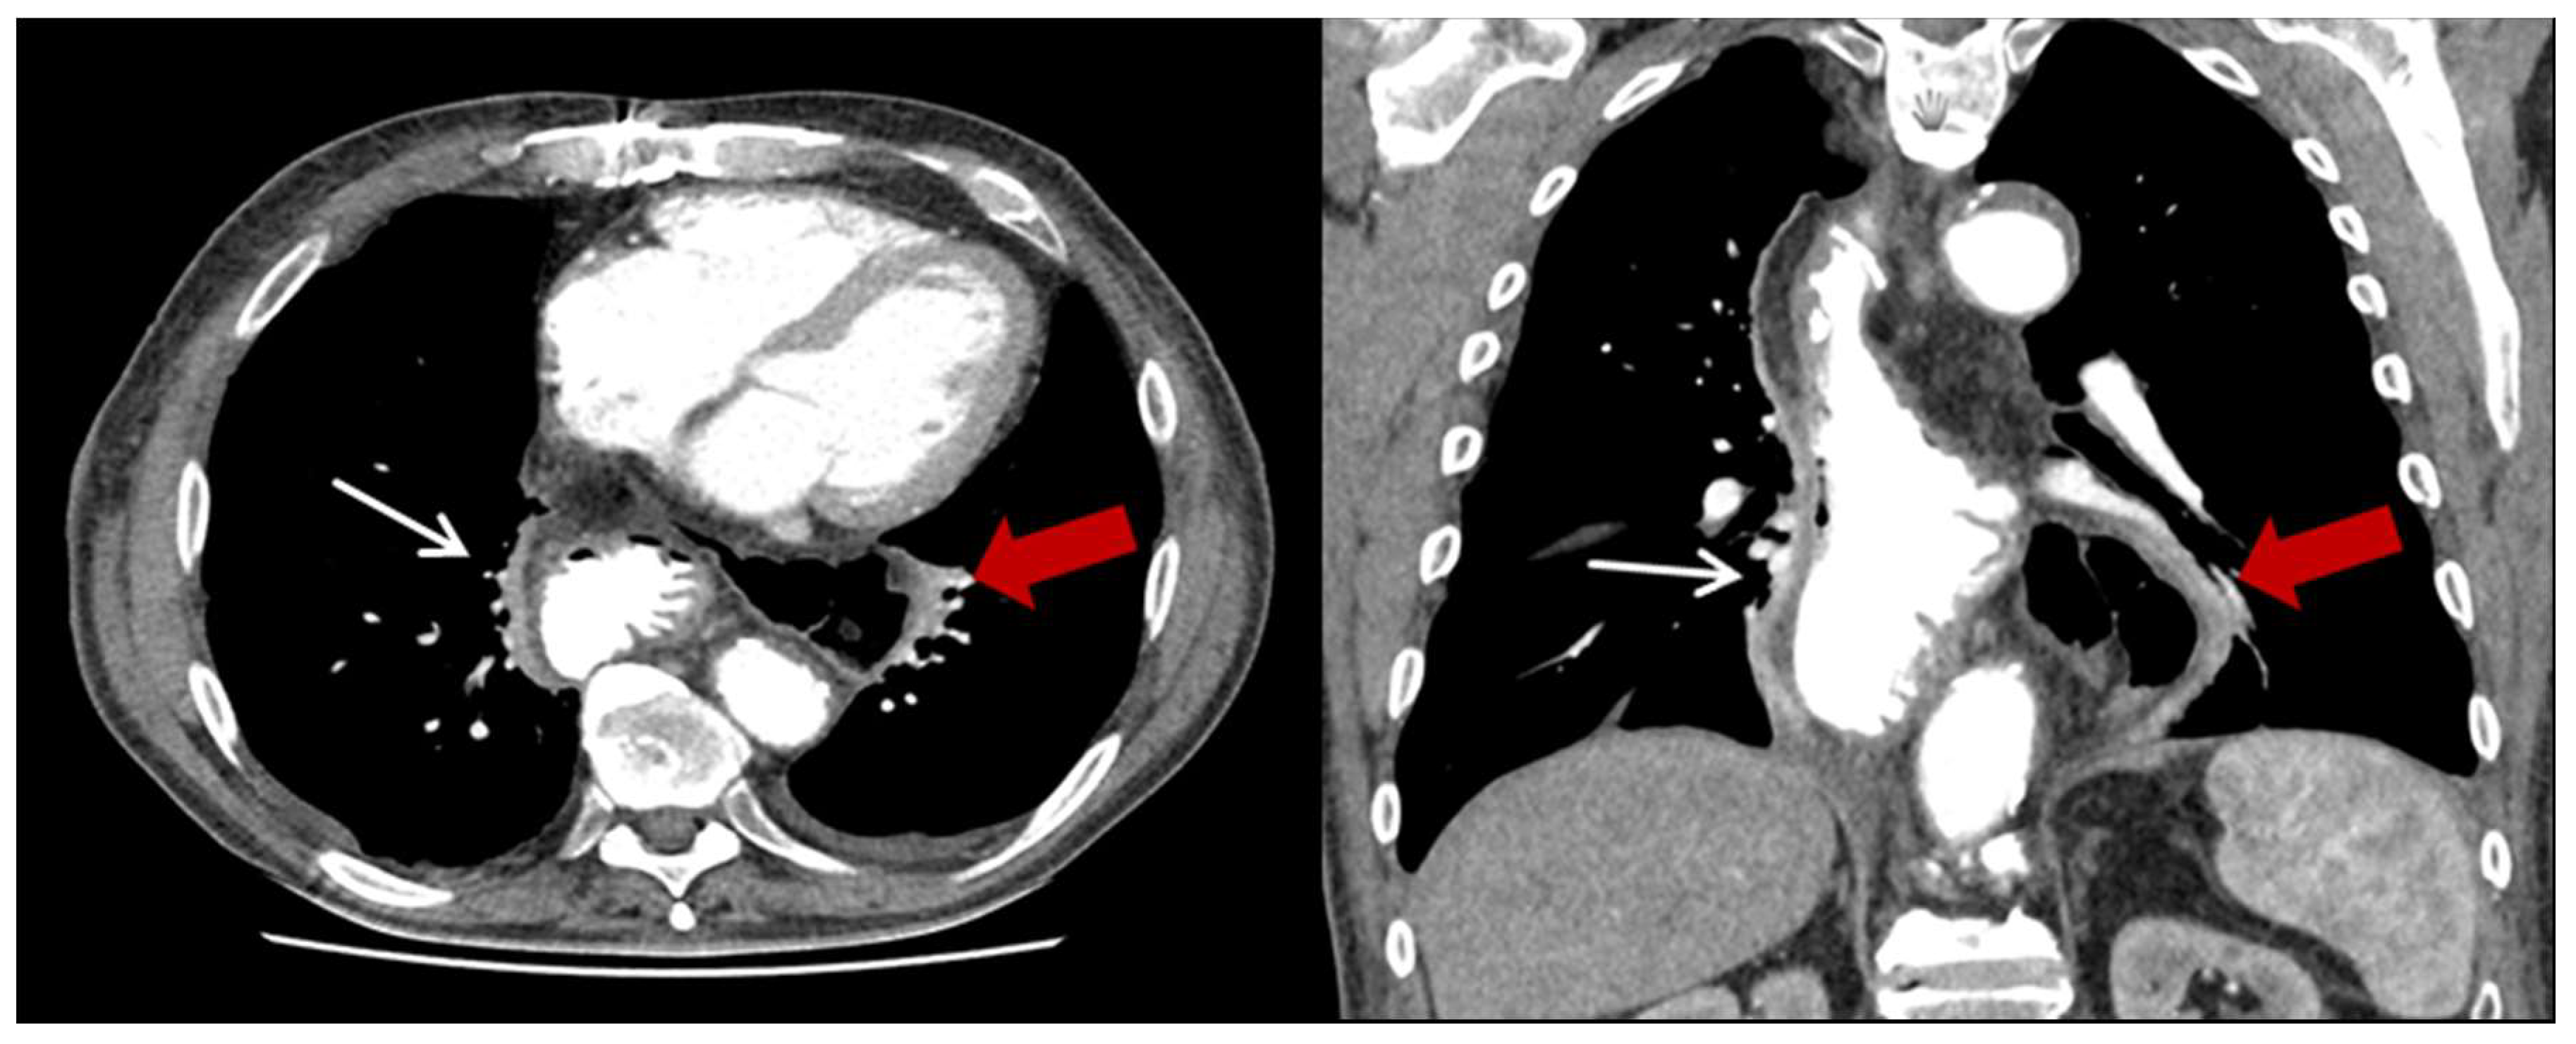

| Characteristics | HH (n = 23) (%) |

| Content of HH, n (%) | |

| Colon | 23 (100) |

| Additionally small bowel | 3 (13) |

| Position of the HH n (%) | |

| Left thoracic side | 18 (78.3) |

| Right thoracic side | 1 (4.4) |

| Both sides | 1 (4.4) |

| Lower mediastinum | 3 (13) |

| Symptoms n (%) | |

| None | 13 (56.5) |

| Abdominal pain and discomfort | 10 (43.5) |

| Ileus/incarceration | 4 (17.4) |